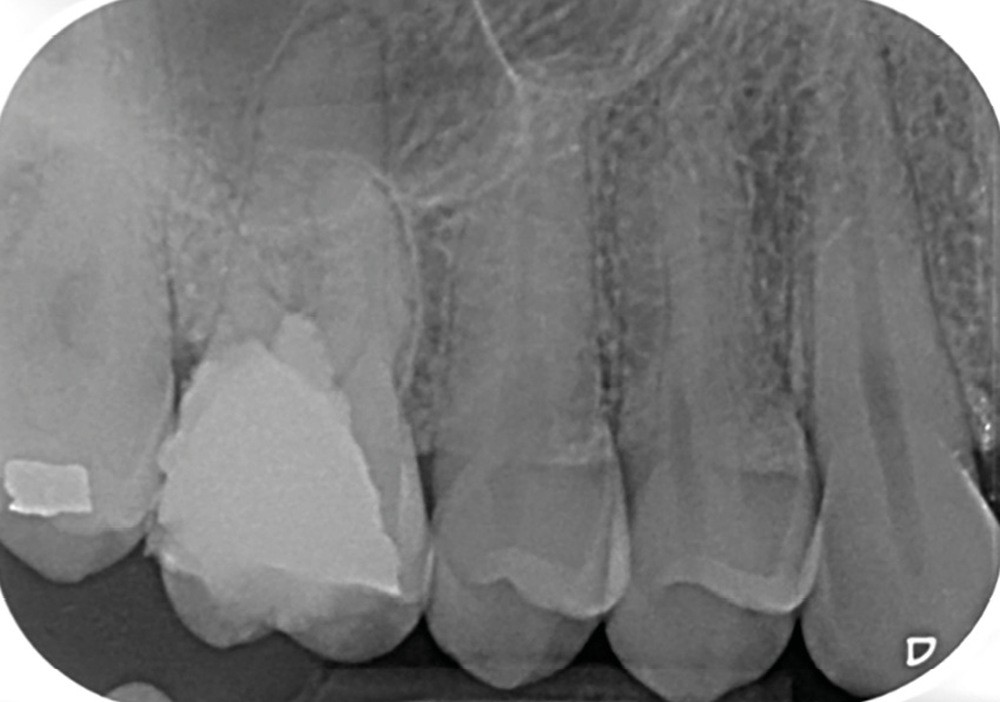

13. si possible, mise en place d’un champ opératoire sur la dent concernée, de sorte à isoler la zone de perforation de toute humidité (fig. 2) ;